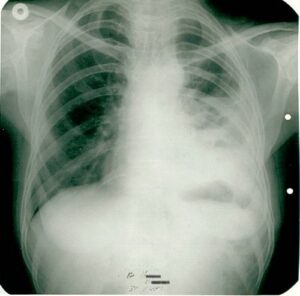

Solid Tumor Research

Innovative approaches in lung, breast, colorectal, and other solid tumors. Combinations of targeted therapy and immunotherapy.